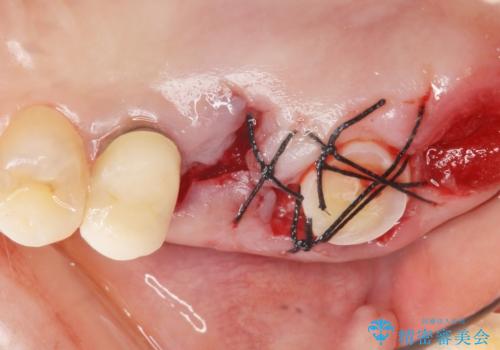

使っていない親知らず(右上8)を右上7抜歯窩に移植し、支台歯としてブリッジによる補綴治療を行いました。

- 外科手術のため、術後に痛みや腫れ、違和感を伴います

- 適応範囲に制限があります(健康な親知らず・移植歯が必要など)

- 移植歯が生着しない可能性があります

- 予後が不安定で歯によっては長く持たない可能性があります